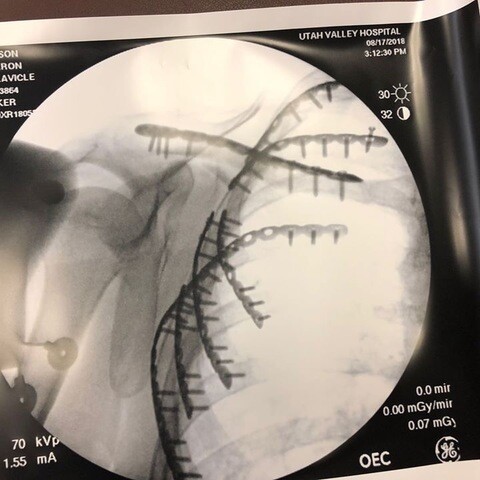

An X-ray of Cameron Johnson’s clavicle and ribs showing pins to repair his seven broken ribs from a motorcycle accident in July 2018.

Emergency room doctors found that Johnson had broken his clavicle and shoulder, along with all the ribs on his right side. He had road rash and a punctured lung. Even though he took the bigger helmet like his son had asked, Johnson still suffered a broken skull and traumatic brain injury, which may have been much worse had he not heeded the prompting of his son. Due to his injuries, Johnson was put into a medically induced coma for several days.

Johnson would require surgery to fix his ribs with seven different plates. He would need to have staples in his head, wear a sling for his clavicle (that would later require surgery), and have two stents put into his lungs. On top of that, the fluid in his lungs caused him to develop pneumonia.